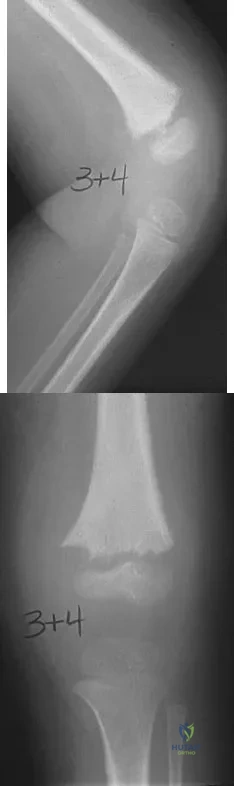

A 16-year-old high school pitcher notes acute pain on the medial side of his elbow during a pitch. Examination that day reveals medial elbow tenderness, pain with valgus stress, mild swelling, and loss of extension. Plain radiographs show closed physes and no fracture. Which of the following diagnostic studies will best reveal his injury?

A 65-year-old woman has had chronic aching discomfort involving her elbow for the past 6 months. Radiographs and a biopsy specimen are shown in Figures 38a through 38c. What is the most likely diagnosis?

Figures 9a and 9b show the radiographs of a 4-year-old child who sustained an elbow injury. What is the most likely complication resulting from this fracture if treated in a cast?